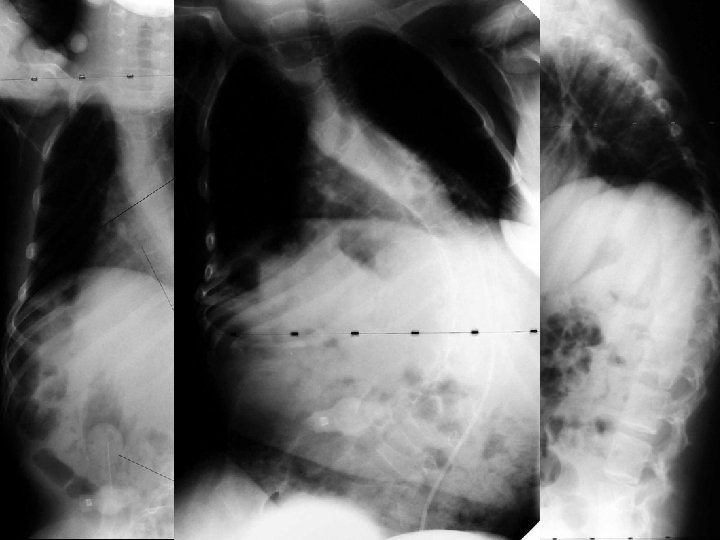

Neuromuscular Curves

Effects of Scoliosis • Pulmonary – Change in shape of chest cavity • Functional – Loss of sitting balance – Loss of upper extremity use